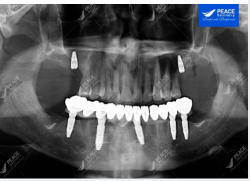

Khôi phục trọn vẹn chức năng ăn nhai và thẩm mỹ cho khách hàng lớn tuổi

Ca lâm sàng: ???-??-? ??????? (??) + ? ??????? ??̀ ??̂̀? ??̆?? ??̛́ (??) → VẤN ĐỀ CHÍNH YẾU: Khách hàng đến Peace Dentistry với tình trạng: ✓ Hàm trên:...